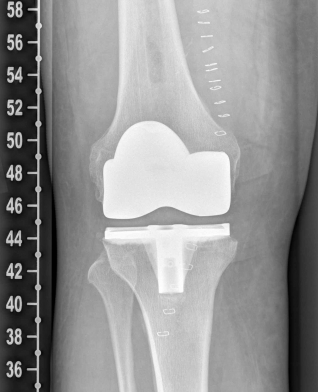

Example X-ray images before and after implantation of a Persona knee prosthesis with robot.

b) nach Implantation der Knie-Totalendoprothese angefertigte Röntgenaufnahmen |